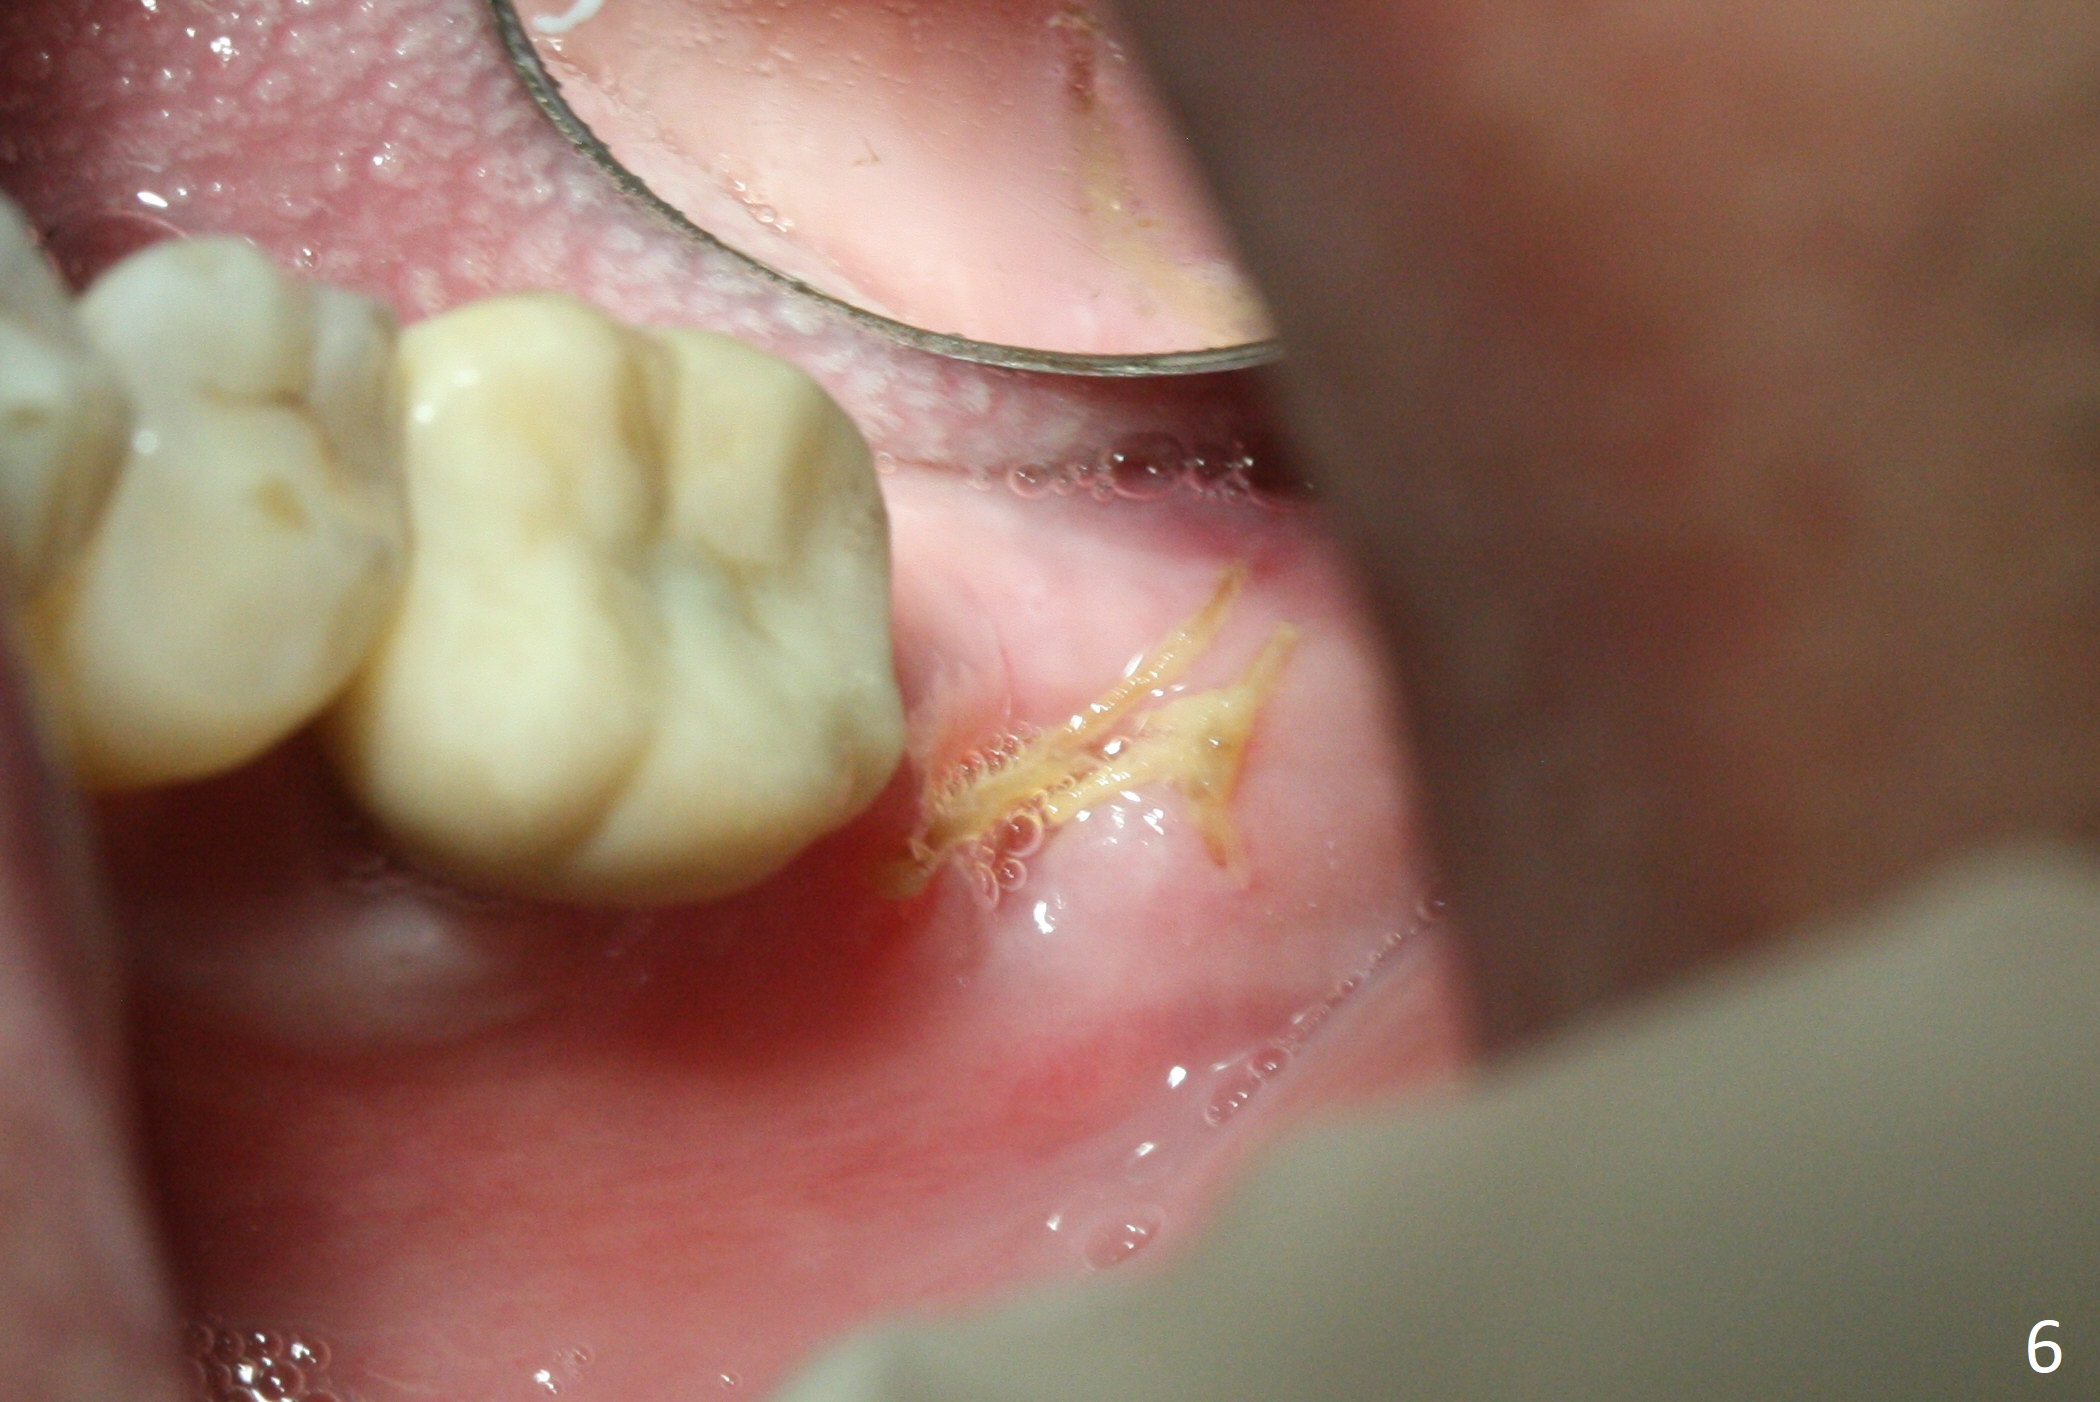

Due to severe furca (Fig.1 *) and distal root (Fig.2 D) infection at #31, there is pain when osteotomy is initiated in the apical native bone for 2 mm after extraction (Fig.3). The distal root is found to have vertical fracture. Socket preservation is performed with Vera Graft, collagen plug and 6-month membrane (Fig.4). In fact it would be possible to initiate osteotomy (Fig.5 white line) in the mesial slope (red dashed line) for implant placement (less infection (far from the lesion), less pain). There is postop pain and swelling, but the symptoms are less 7 days postop (Fig.6). The patient returns 6 months post socket preservation (Fig.7). The bone density at the healed socket is high (>1000 units); a 5x10 mm implant will be placed with guide (Fig.8). After implant placement at #18, make a buccal incision to explore the buccal gingival defect at #19 (Fig.9, 1), most likely due to extra bone graft.